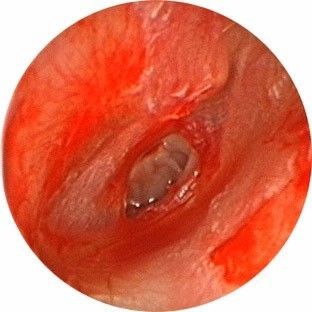

检查可见鼓膜多呈现裂隙状穿孔,穿孔边缘有少量血迹,外耳道有时可见血迹或血痂。若出血量较多或有水样流出,提示颞骨骨折或颅底骨折导致脑脊液耳漏。